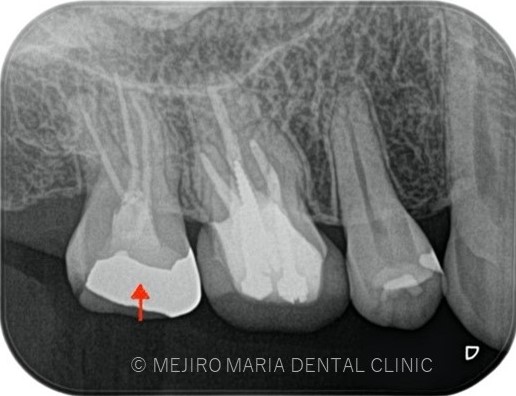

右上7番には臨床症状(叩くことでの痛み)が確認できるものの、レントゲン上には根尖性歯周炎と判断できる透過像(病変の影)は確認できませんでした。歯科用CTを撮影してみると、近心根と遠心根に明らかな病変を認めました(歯科用CT画像1赤丸)。他の臨床症状と歯科用CT画像から右上7番の根尖性歯周炎と診断しました。

また、同時に近心根には見逃している根管もしくはフィンと言われる極小なスペース(CT画像2赤丸)が存在することも確認できます。

治療中に歯科用顕微鏡(マイクロスコープ)下にてCT画像で確認した部位には手つかずの根管を確認し、処置を行った。